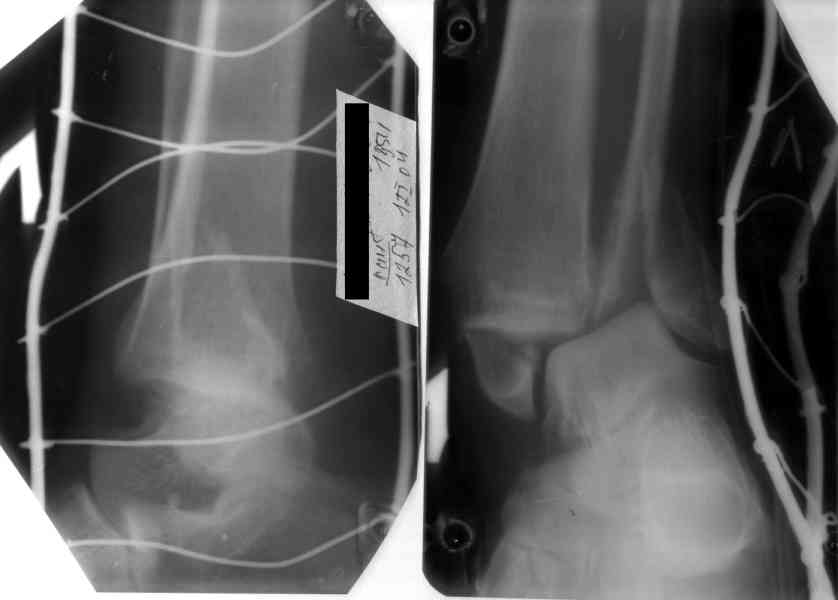

Re: Перелом обеих лодыжек и з/края б/б кости с выв

После проведенной дискуссии пришел к выводу, что трансартикулярная диафиксация не совсем приемлима с учетом современных методик остеосинтеза. Кроме того, вычитал, что хрящ разрушается на расстоянии до 0,5 см от места проведения спицы.

Пока я был в интернатуре, предпочитали осуществлять стабильный остеосинтез с ранней функцией. См. приложения и полнотекстный вариант

статьи.